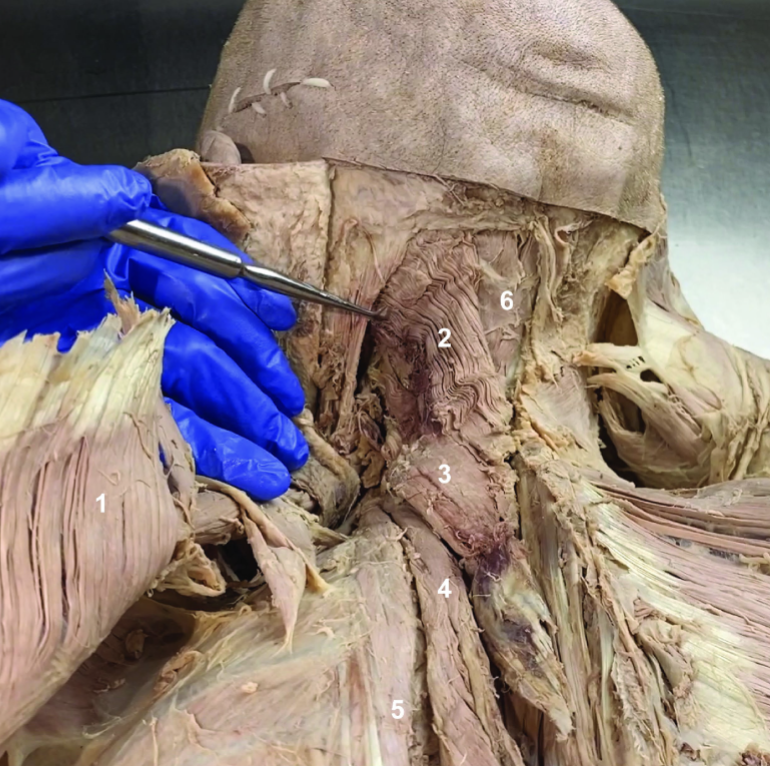

Trapezius (reflected)

ID structure

Spinal accessory n. (CN XI)

ID structure

Transverse cervical a.

ID structure

Levator scapulae

ID structure

Rhomboid minor

ID structure

Rhomboid major

ID structure

Rhomboids (reflected)

ID structure

Splenius capitis

ID structure

Splenius cervicis

ID structure

Longissimus

ID structure

Iliocostalis

ID structure

Semispinalis capitis